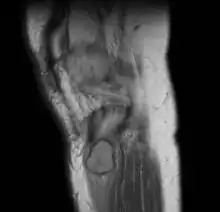

MRI right knee: periosteal chondroma